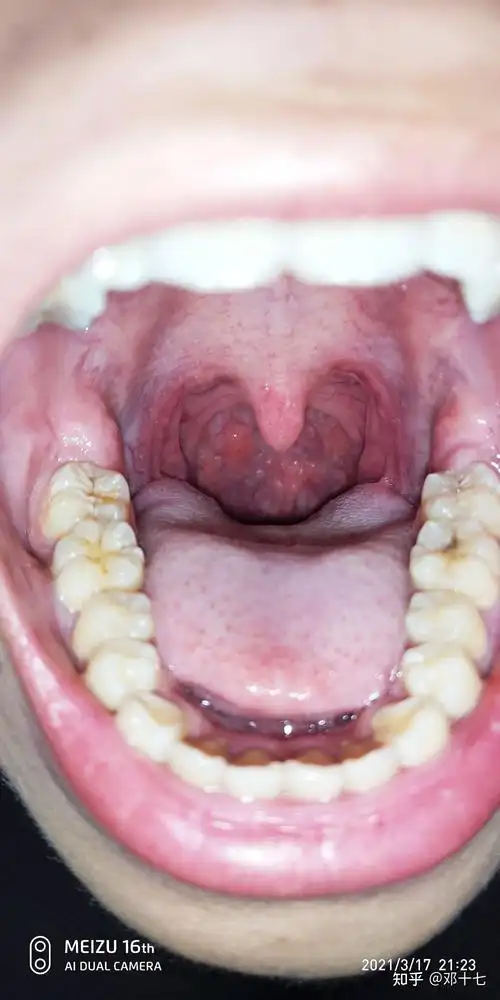

慢性咽炎

记录治疗慢性咽炎过程2

今天我们来说一说滤泡性咽炎,中医上它属于慢性咽炎的其中一类,非常

慢性咽炎的检查